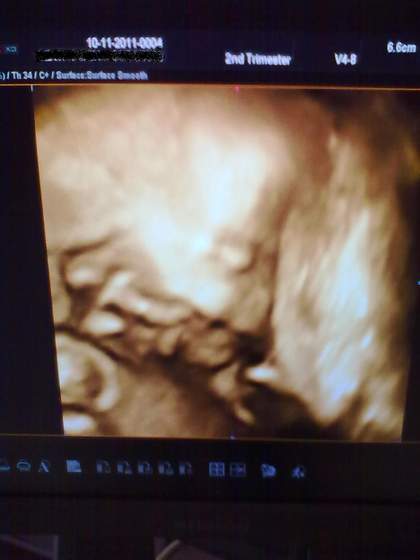

zdjecie kiepskie, bo telefonem w pospiechu:) - drukarka szpitalna nie wspolpracowala z nowym sprzętem niestety:) maluszek wtulony w mame, az nosek sobie zmiażdżył... usmieszek jest :)... tylko tam pępowina nam przeszkodzila troszeczke i nachodzila na buziunie:)

Bobas - 23t5d.jpg